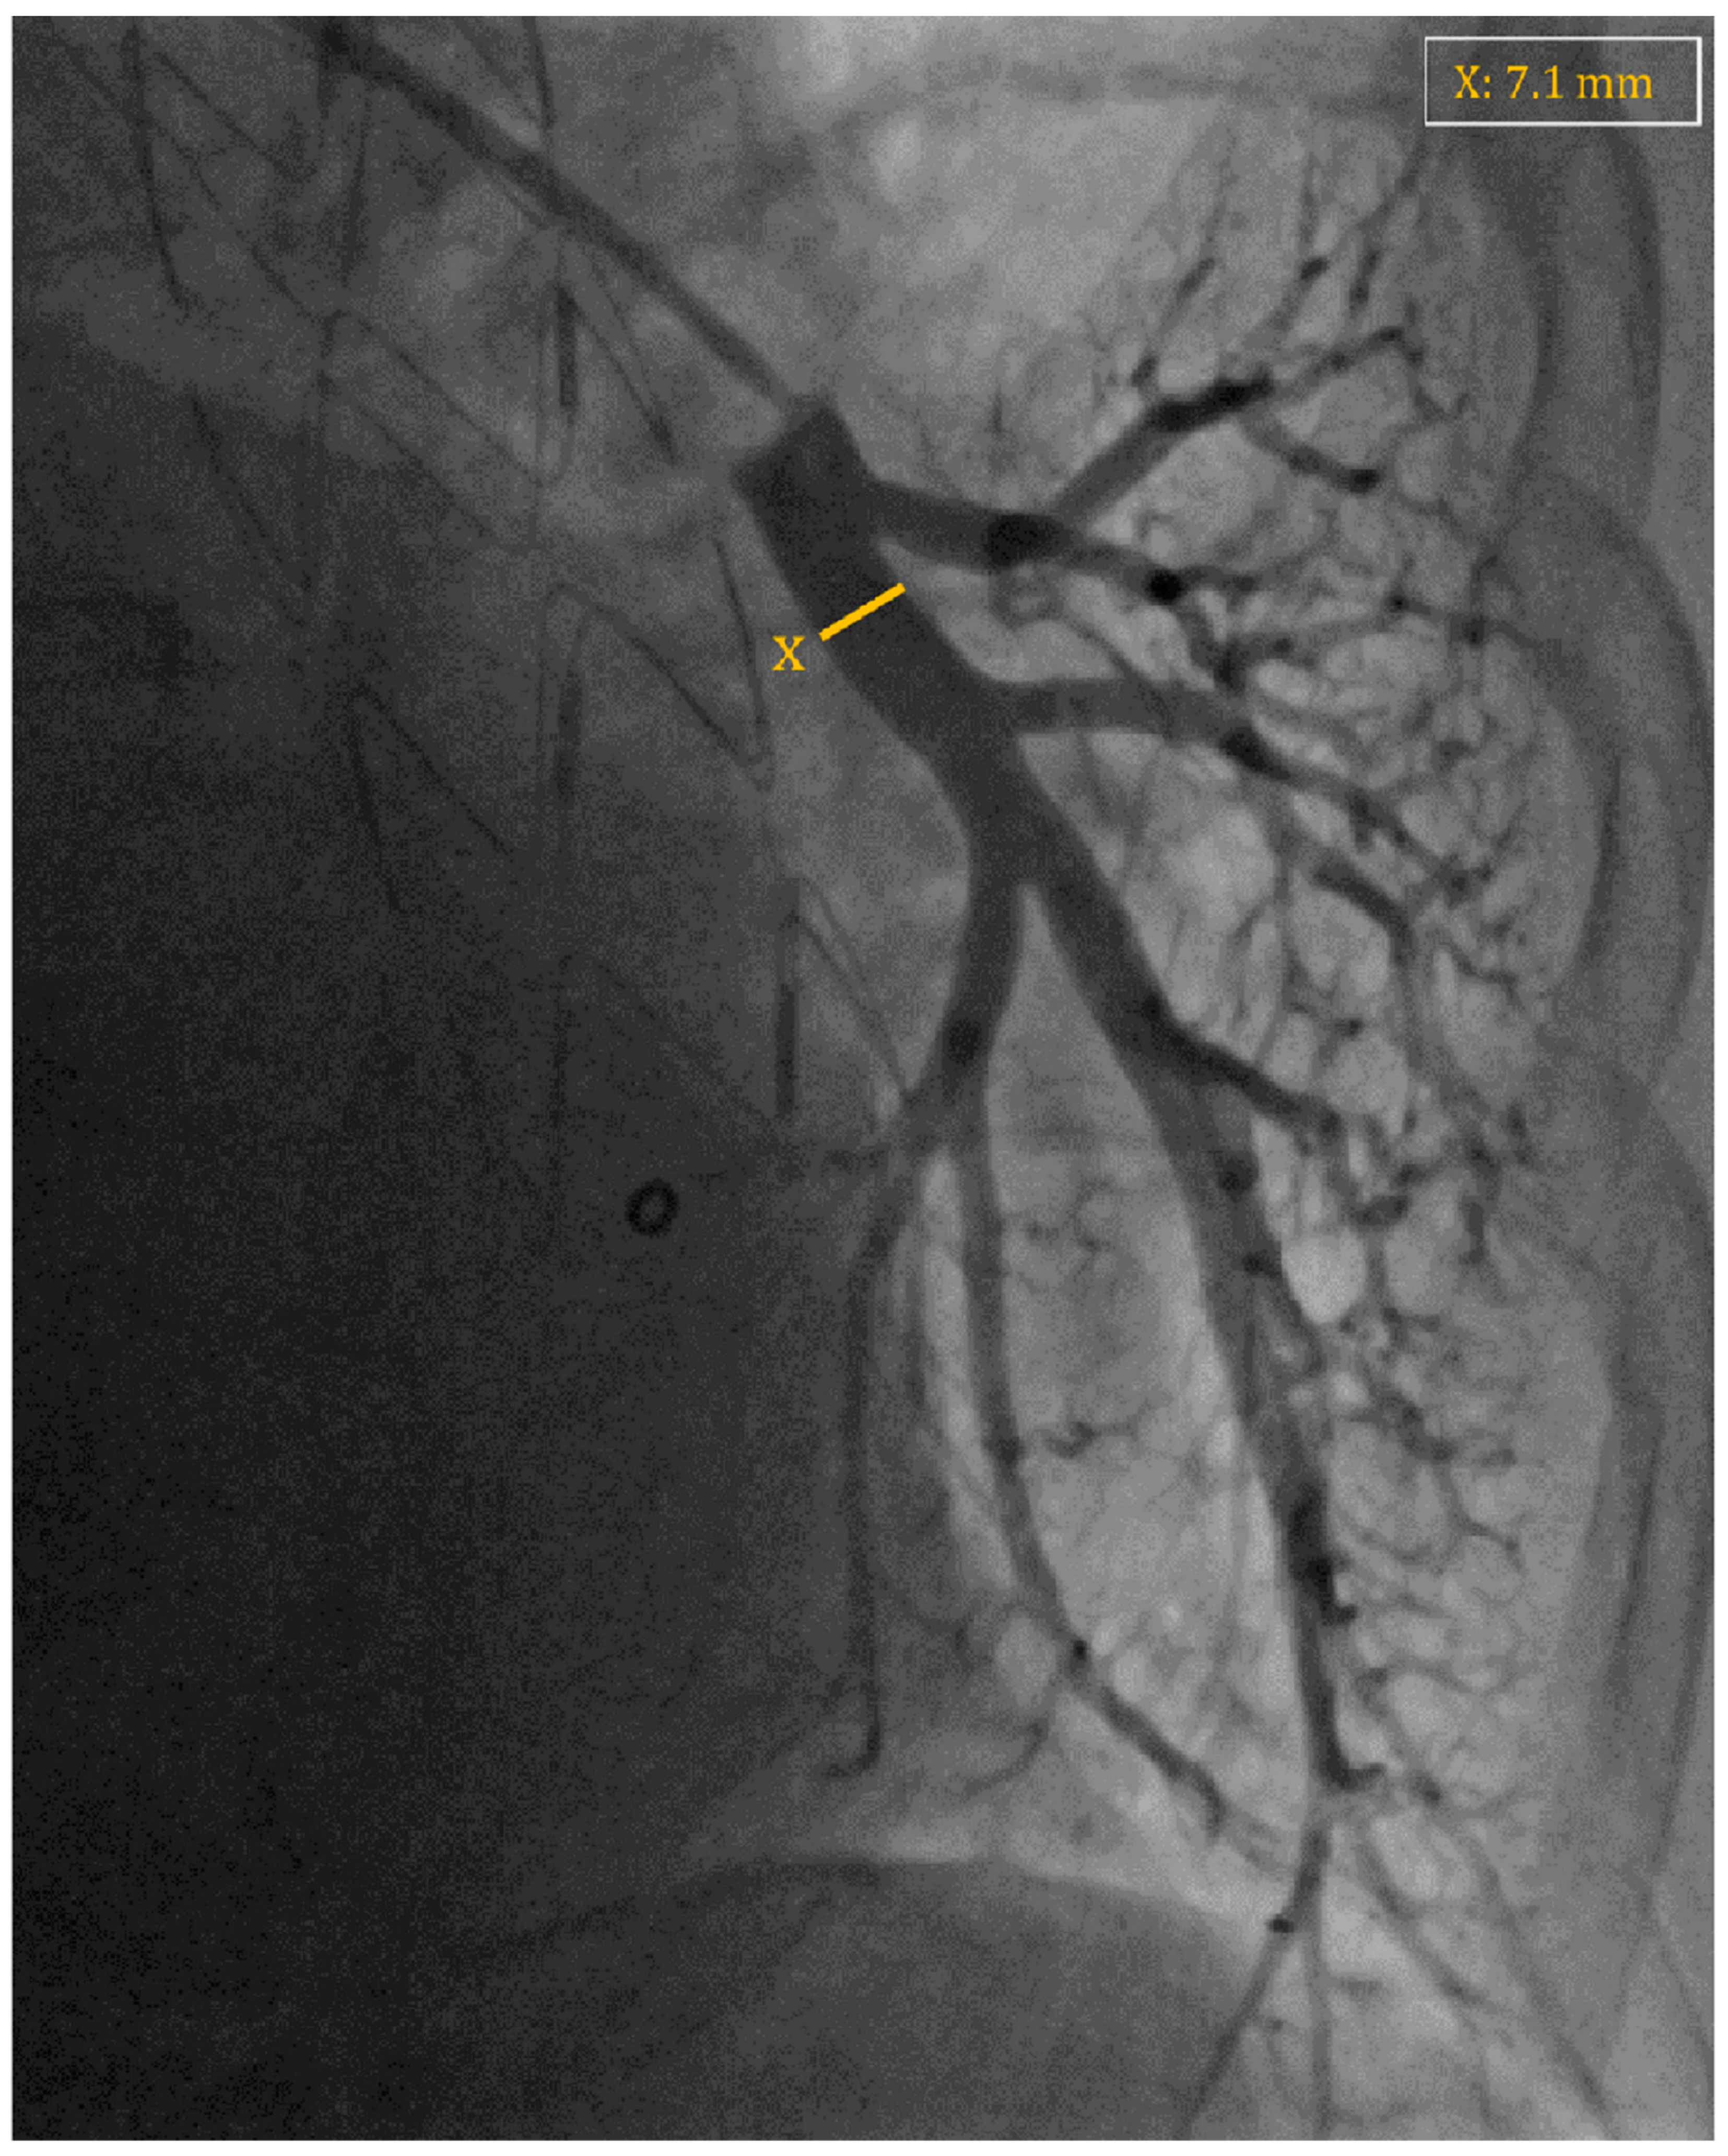

7. Implant Procedure

- Shavelle, D.; Jermyn, R. The CardioMEMS Heart Failure Sensor: A Procedural Guide for Implanting Physicians. J. Invasive Cardiol. 2016, 28, 273–279. [Google Scholar] [PubMed]